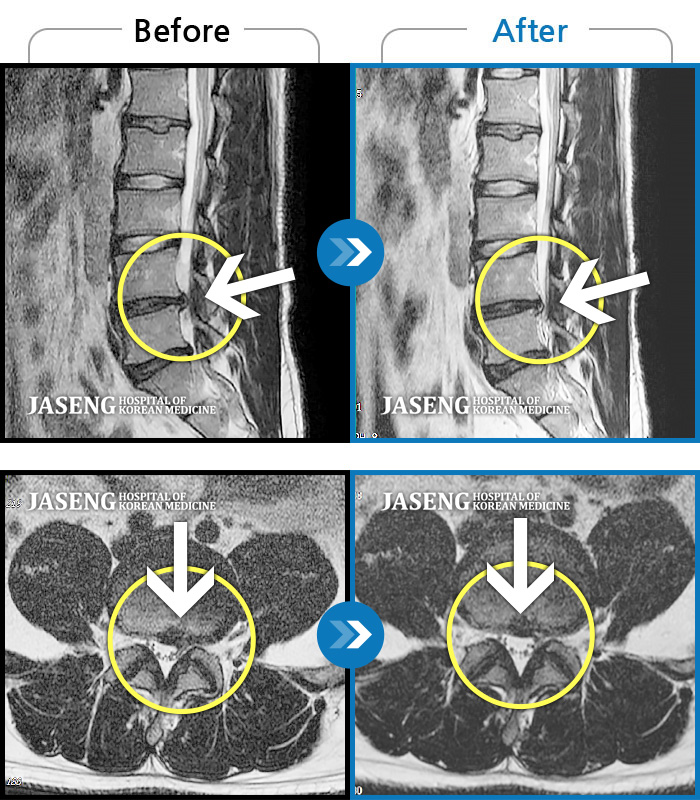

허리디스크

인천 · 강아현 원장

허리와 우측 다리가 아파서 걸을 수도, 바로 누울수도 없어요

촬영시기

2020.05.18 ~ 2021.01.20

2021.01.25

조회수 127